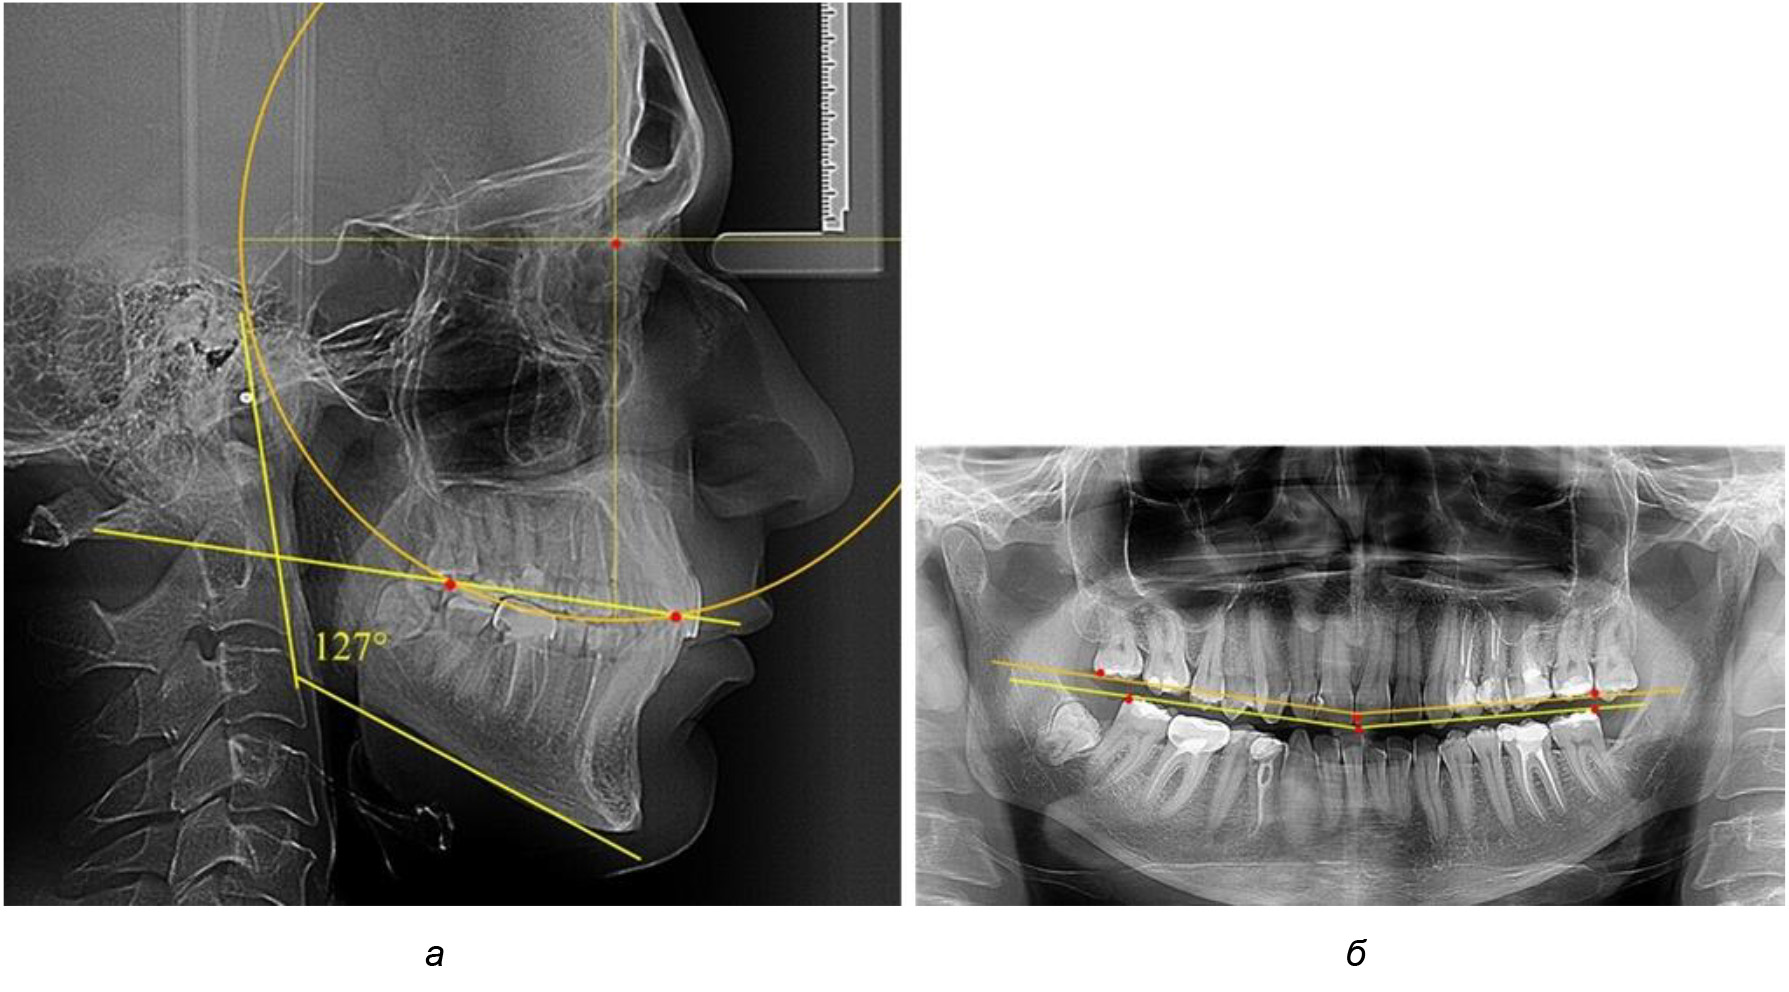

У людей с аномалиями окклюзии по сагиттали в 1-й подгруппе обследовано 9 человек. Обращает на себя внимание увеличение глубины кривой Spee, что нами расценивалось, как патологическая форма кривой линии окклюзии.

Глубина кривой Spee в среднем по 2-й подгруппе составила (5,69 ± 1,57) мм, что было достоверно больше, чем у людей с физиологической окклюзией (р ˂ 0,05). Достоверных различий с показателями, полученными при анализе ТРГ и ОПТГ, нами не отмечено (р ˃ 0,05). Отношение радиуса окружности к сагиттальному размеру окклюзионной линии в среднем по подгруппе составляло 1,372 ± 0,042 и не соответствовало числу Фибоначчи, что может быть использовано в качестве диагностического критерия определения патологической формы кривой Spee. После лечения пациентов техникой «прямой» дуги было отмечено незначительное увеличение сагиттального размера окклюзионной лини в среднем на (2,12 ± 0,77) мм. Однако окклюзионная линия практически касалась окклюзионного контура всех жевательных зубов, и отмечалось практически полное отсутствие кривой Spee.

Таким образом, проведенное лечение техникой «прямой» дуги способствует нормализации окклюзионного равновесия и торку передних зубов, однако не соответствует оптимальному окклюзионному статусу, характеризующему физиологическую окклюзию. При этом величина нижнечелюстного угла оставалась на прежнем уровне (рис. 5).

Рис. 5. Особенности ТРГ при патологической кривой Spee до лечения (а) и после лечения (б) техникой «прямой» дуги

Во 2-й подгруппе 2-й группы было обследовано 7 человек.

Обращает на себя внимание, что глубина кривой Spee в анализируемой подгруппе практически не отличалась от показателей, полученных у людей с физиологической окклюзией, и составляла (4,23 ± 1,58) мм. Отношение радиуса окружности к сагиттальному размеру окклюзионной линии в среднем по подгруппе составляло 1,623 ± 0,02 и соответствовало числу Фибоначчи.

После лечения пациентов техникой «прямой» дуги, так же как и в 1-й подгруппе, было отмечено увеличение сагиттального размера окклюзионной лини в среднем на (2,38 ± 0,83) мм. Окклюзионная линия практически касалась окклюзионного контура всех жевательных зубов, и отмечалось практически полное отсутствие кривой Spee, так же как и у людей 1-й подгруппы 2-й группы (рис. 6).

Рис. 6. Особенности ТРГ при оптимальной кривой Spee до лечения (а) и после лечения (б) техникой «прямой» дуги

Таким образом, проведенное лечение техникой «прямой» дуги способствует нормализации окклюзионного равновесия и торку передних зубов, однако не соответствует оптимальному окклюзионному статусу, характеризующему физиологическую окклюзию. При этом величина нижнечелюстного угла оставалась на прежнем уровне.